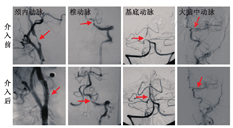

DSA是在脑血管中(动脉和静脉均可)注射造影剂,然后进行系统处理,使血管显示地更加清晰,便于医生诊断或进行手术。DSA所需的造影剂量少、浓度低、X线吸收量少,而对比度分辨率高,可展现脑部所有血管(颈内动脉系统和椎动脉系统)不同部位、不同狭窄程度的管腔及不同部位、不同大小的动脉瘤等(图10,图11),是脑血管病变检查的"金标准"。

PCoA:后交通动脉;ACoA:前交通动脉;MCA:大脑中动脉;PCA:大脑后动脉

DSA可用于各种目的的脑血管检查,包括脑血管病的病因检查,如颈部血管和脑血管狭窄、动脉瘤、动脉夹层(图12)、静脉血栓形成、动静脉瘘等;急诊动脉取栓、动脉溶栓以及脑动脉狭窄支架的介入治疗。